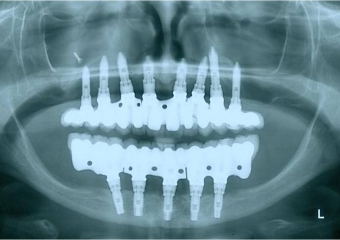

Raio X final, com as próteses em porcelana já instaladas - Clínica Cliniface

Raio X final, com as próteses em porcelana já instaladas